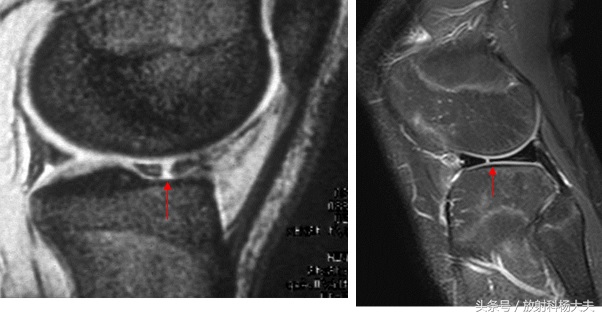

膝关节半月板、十字韧带损伤

毋庸置疑,最佳的检查手段就是MRI了。用MRI可以检查有无断裂,断裂的程度,以及是否需要手术,手术后的效果等等。包括前后交叉韧带,内外侧副韧带,髌韧带,腘肌腱、股四头肌肌腱等等,膝关节周围的韧带都能在MRI上得到准确的识别和诊断。

半月板断裂

前十字韧带断裂